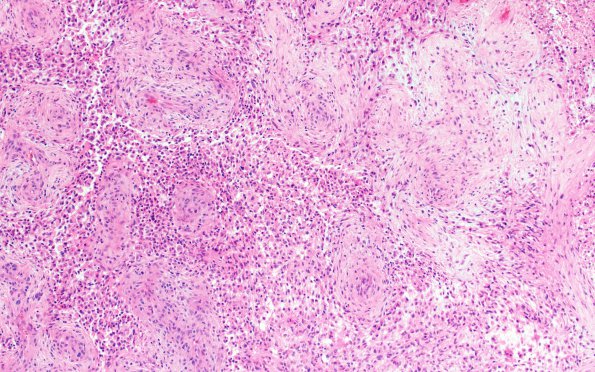

18A4 Gliosarcoma (Case 18) H&E 10X

Higher magnification image of 18A1 (H&E)